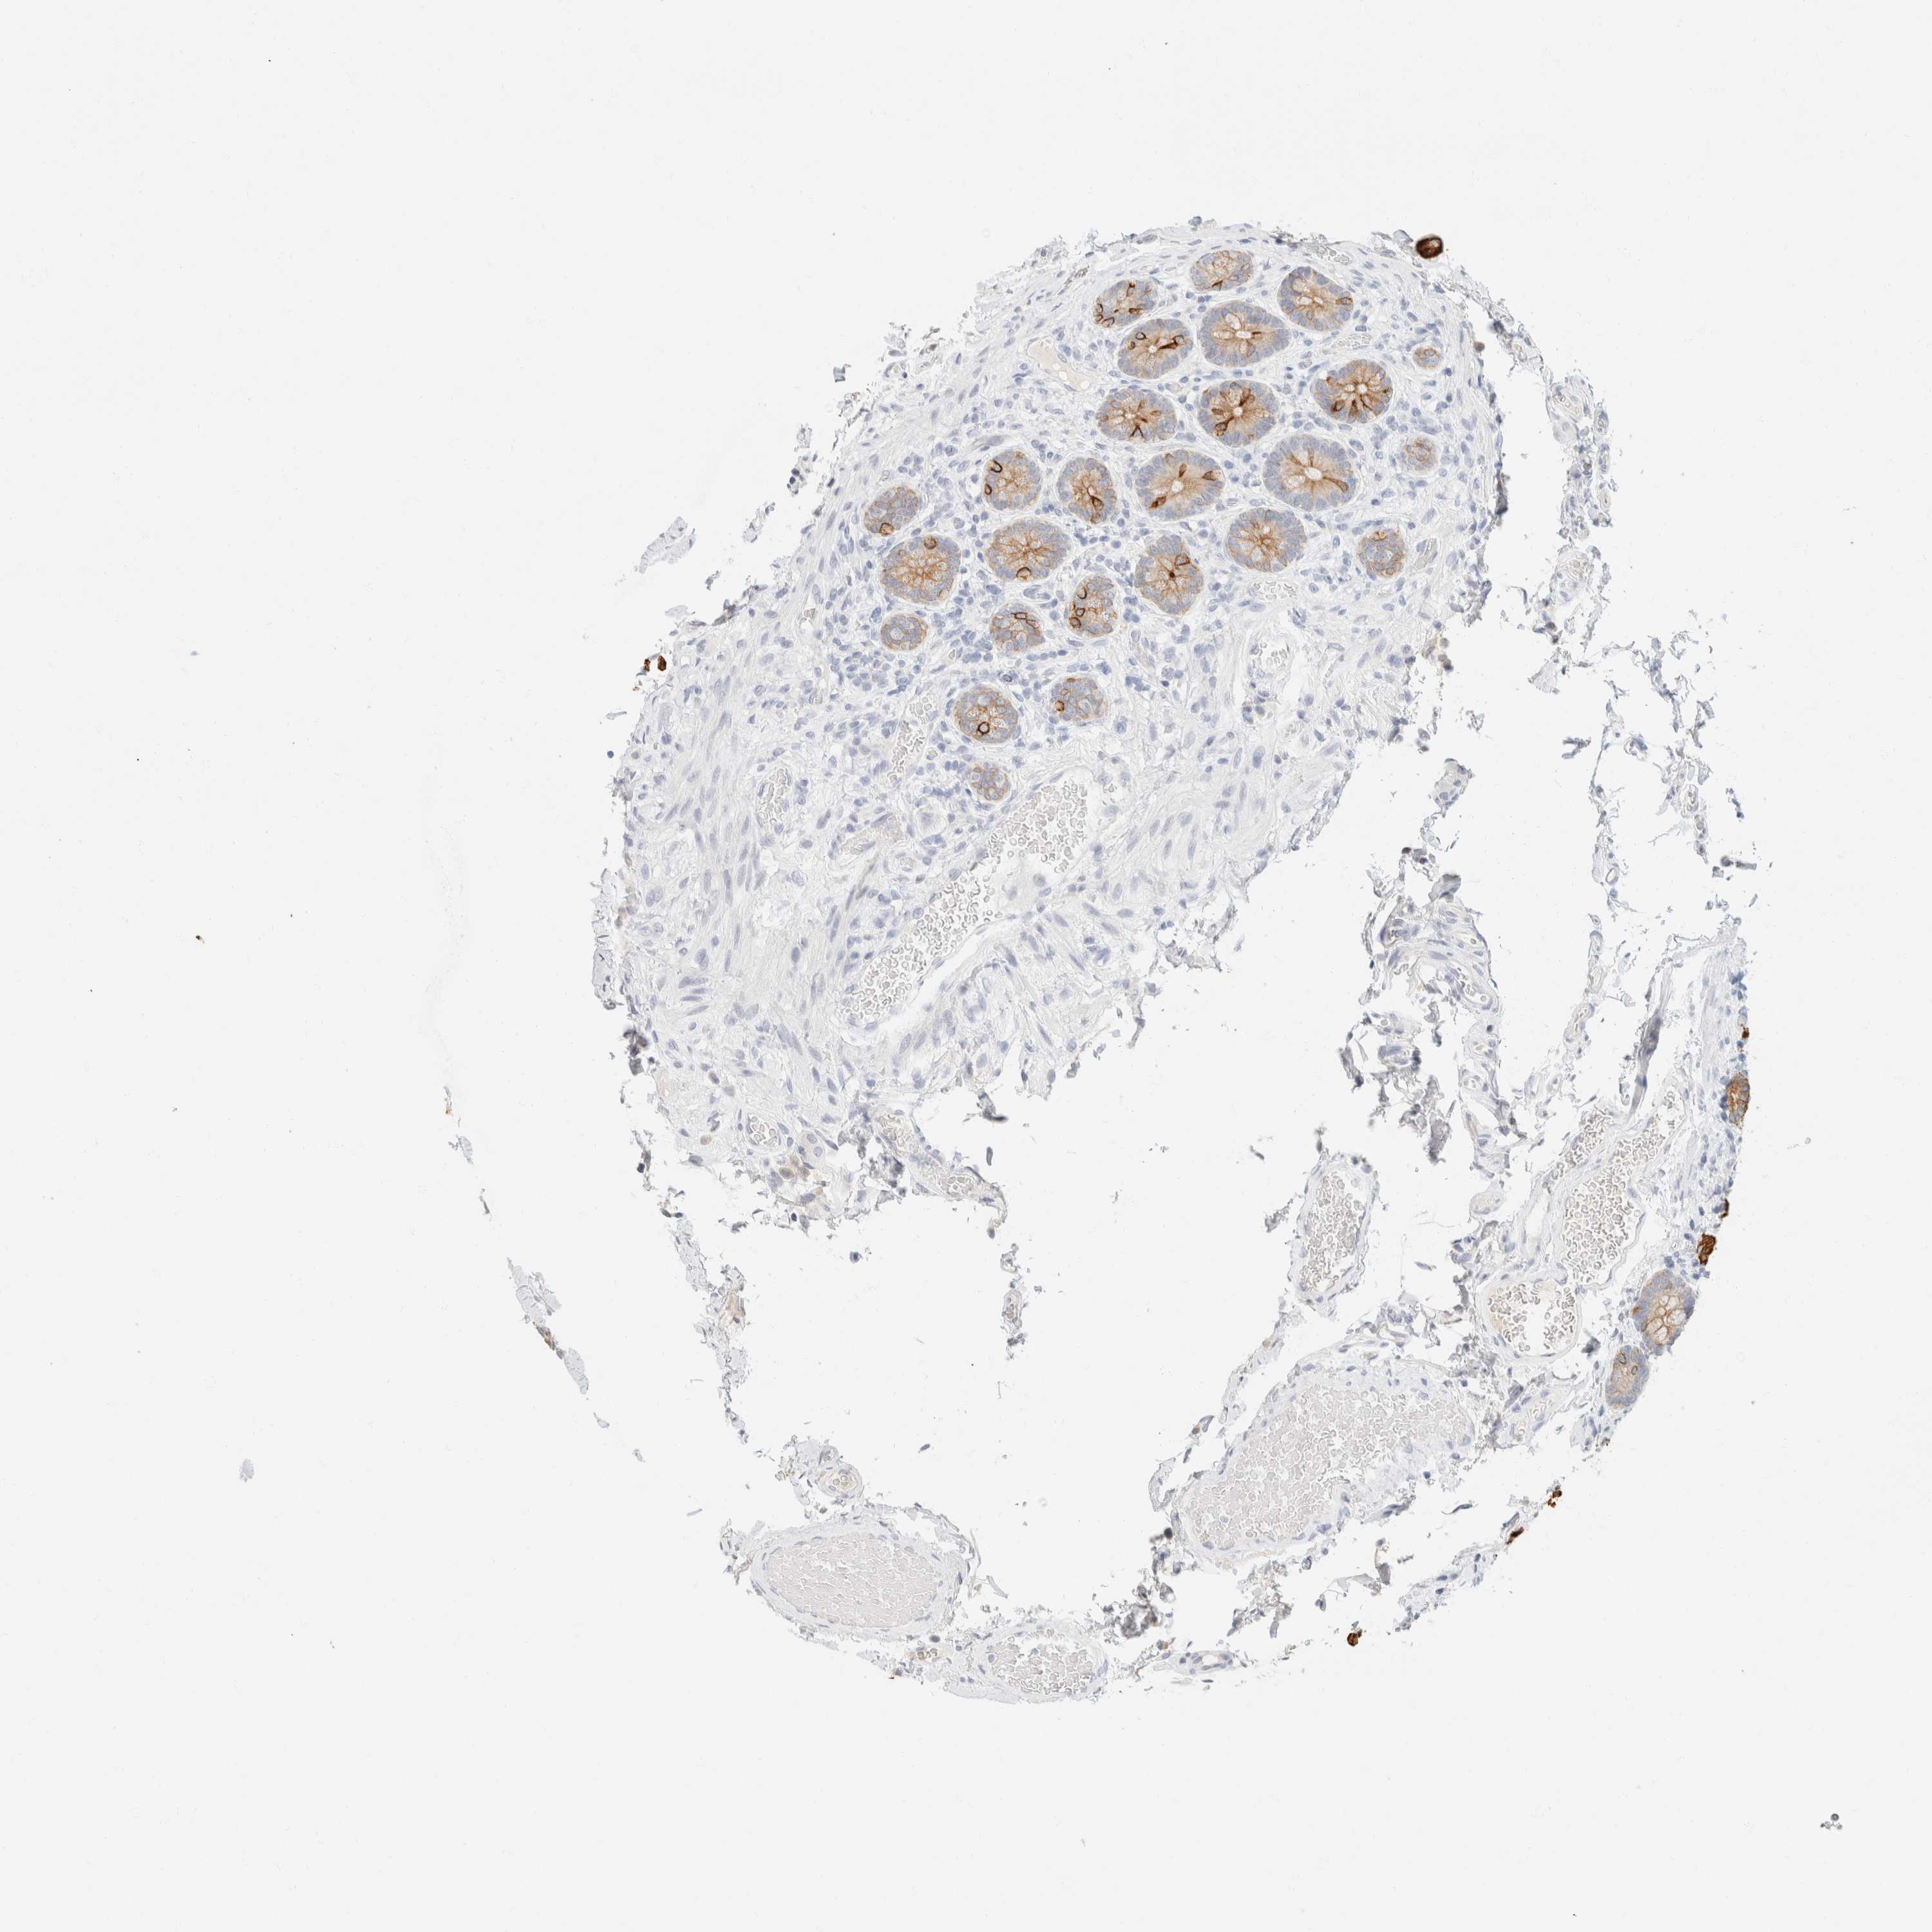

SMALL INTESTINE - Antibody stainingi

Antibody staining in the annotated cell types in the current human tissue is reported as not detected, low, medium, or high, based on conventional immunohistochemistry profiling in selected tissues. This score is based on the combination of the staining intensity and fraction of stained cells.

Each image is clickable and will lead to virtual microscopy that enables deeper exploration of all samples and also displays staining intensity scores, fraction scores and subcellular localization as well as patient and tissue information for each sample.

Antibody HPA024309Antibody HPA024684Antibody HPA027236Antibody CAB000032

Endocrine cells ---High

Enterocytes ---High

Enterocytes - Gradient ---Ascending

Enterocytes - Microvilli ---High

Glandular cells HighHighHigh-

Goblet cells ---High

Paneth cells ---Not detected